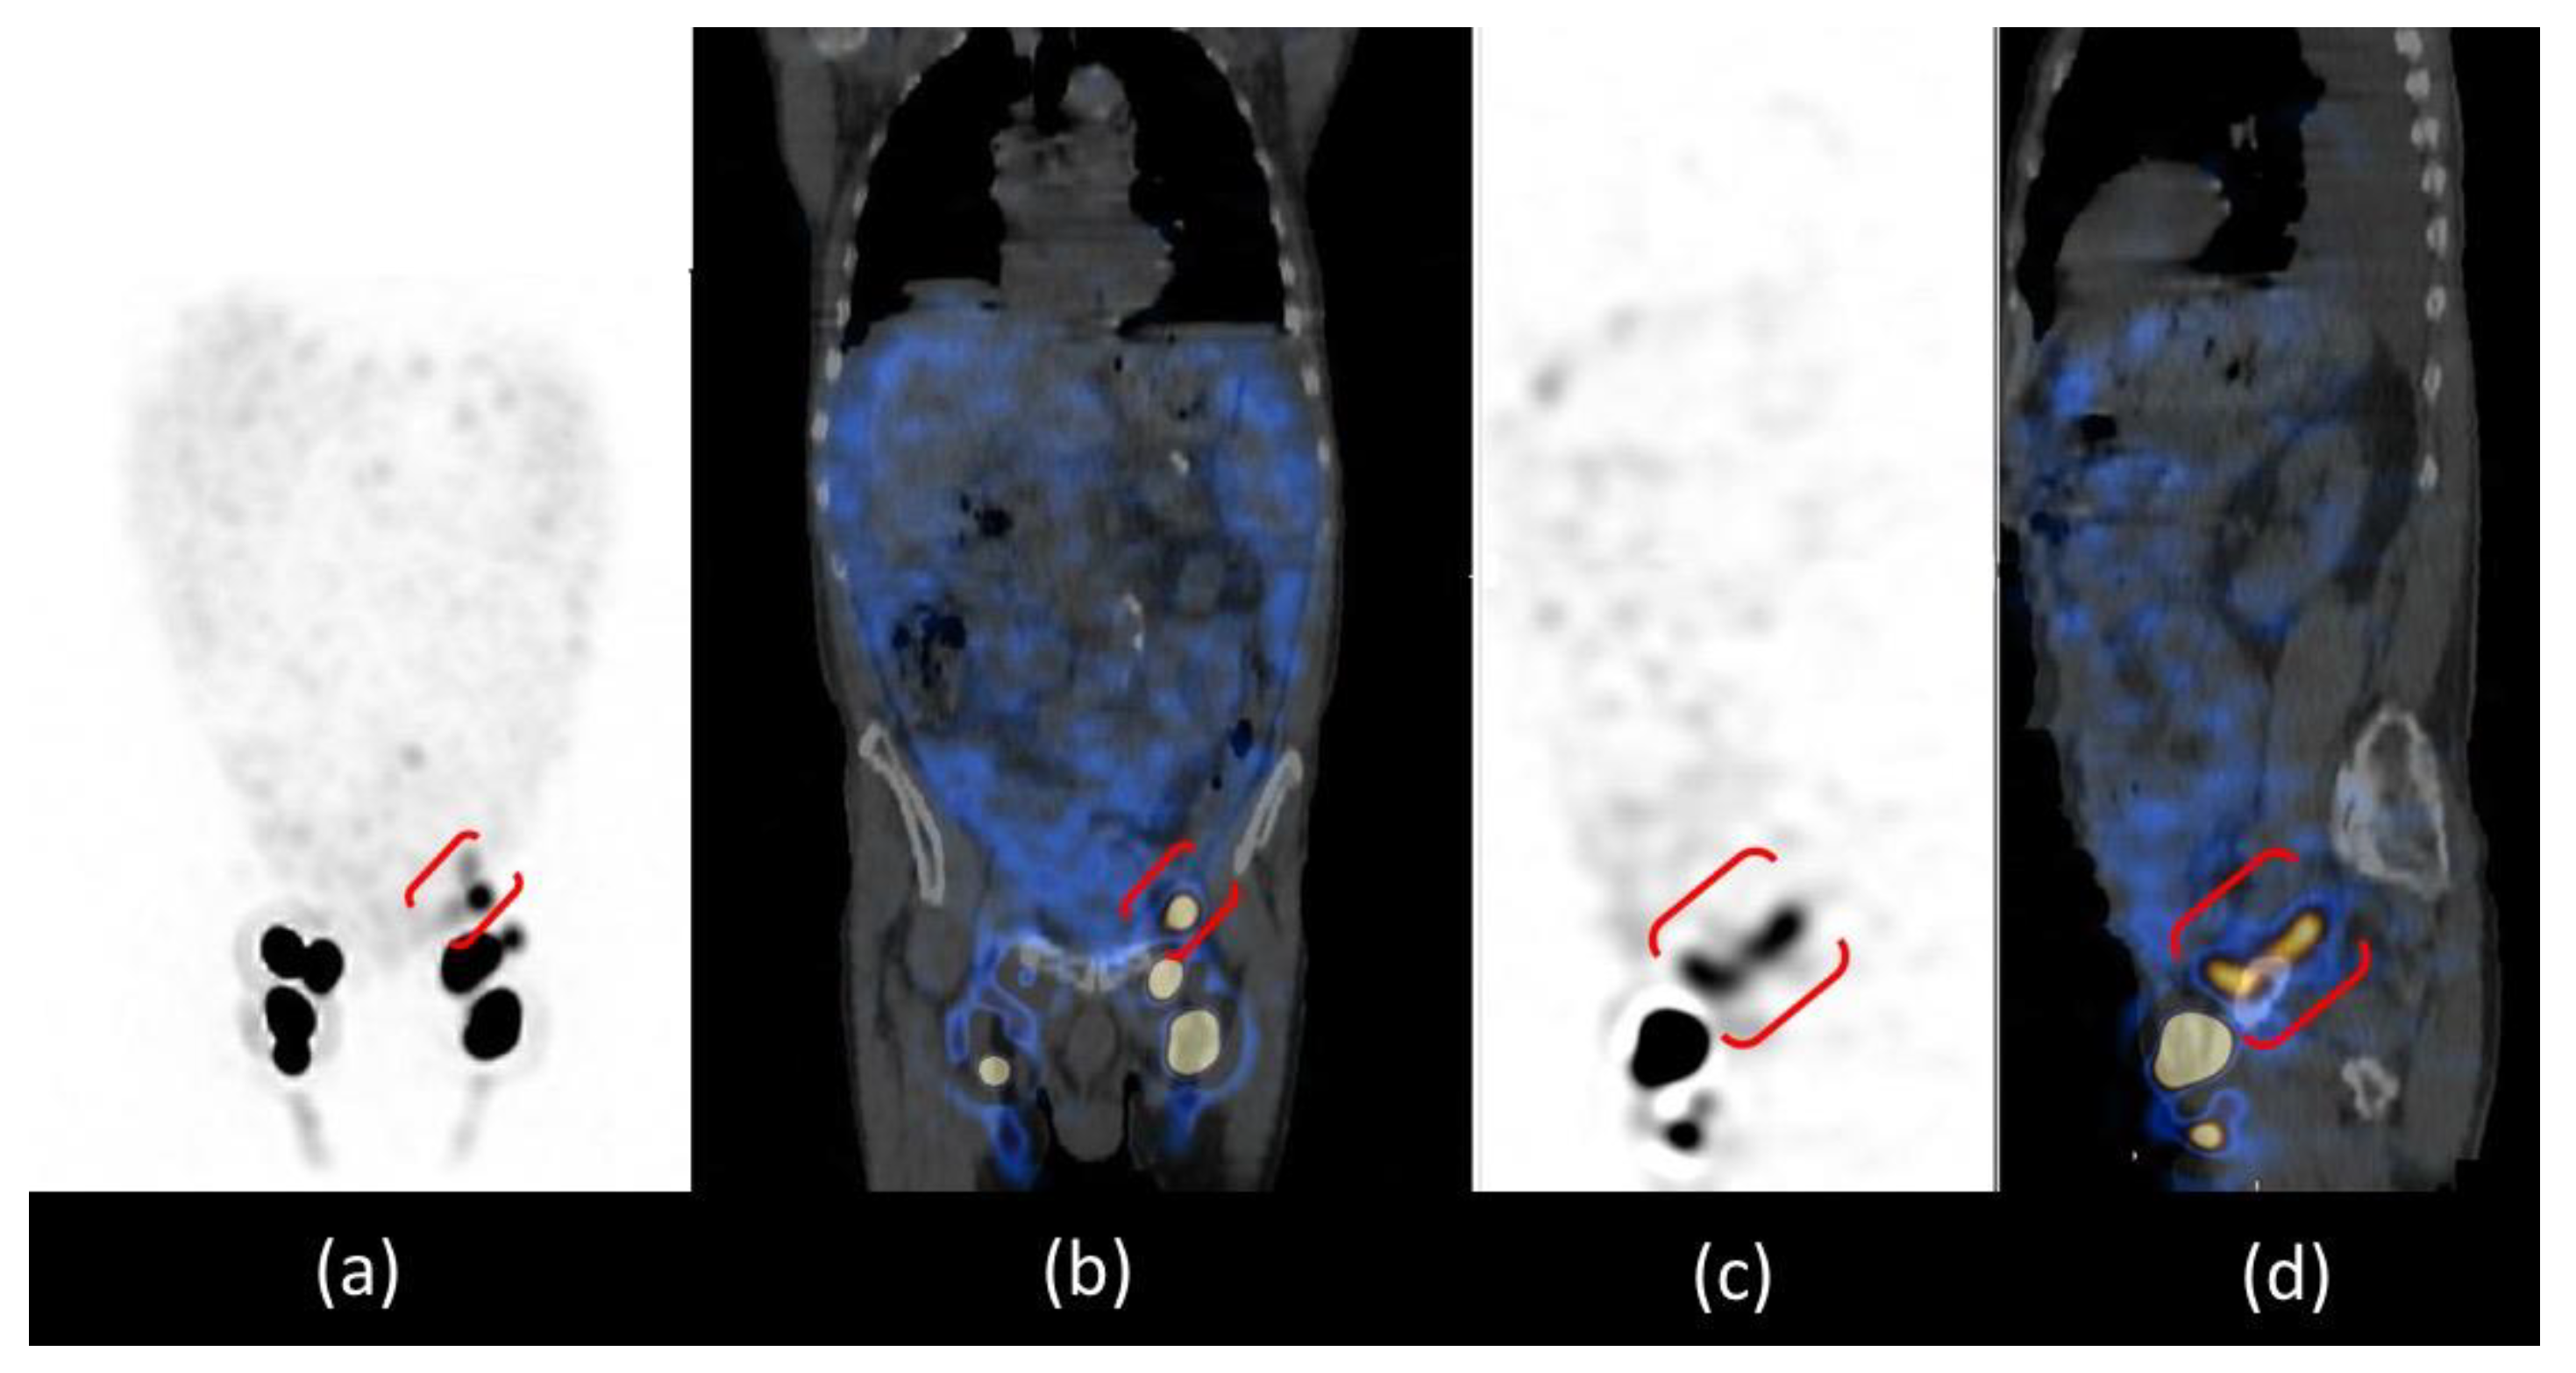

The patient was positioned supine and a dynamic anterior image of the pelvic region was acquired with a rate of 1 frame per min for 20 min that showed only the left inguinal lymph node, revealing delayed and asymmetric lymphatic drainage from lower limbs. After, anterior whole-body images were acquired at 30 and 60 min and after a high-fat meal at 2 and 3 h after administration (Figure 3). Images at 30 and 60 min confirmed the asymmetric lymphatic drainage with delayed visualization of the right inguinal lymph node (Figure 3a,b). Delayed acquisitions after a high-fat meal, showed diffuse pathological abdominal accumulation of 99mTc-labelled human serum albumin nanocolloids; furthermore, a radioactivity spot was visualized in the left iliac region where all internal iliac lymph nodes should have been removed by surgery (Figure 3c,d).

Figure 3.

Anterior whole-body lymphoscintigraphy with 99mTc-labelled human serum albumin nanocolloids performed at the 30th minute (a) and at the 1st hour (b) after administration showed delayed and asymmetric lymphatic drainage of lower limbs. The anterior scans performed after a high-fat meal at the 2nd (c) and 3rd hours (d) showed bilateral inguinal lymph nodes, one focal spot of radiotracer uptake in the left iliac region (red arrows) and diffuse smooth abnormal abdominal radiotracer uptake (green arrows). R = right side; L = left side.

Abdominal SPECT/CT images confirmed the radioactive spot in the left iliac region and the diffuse abnormal accumulation of radiotracer in the peritoneum more intense in the left iliac fossa; the CT co-registration images showed that there was no internal iliac lymph node in that site but a dilatation of the lymphatic pathway at the site of surgical interruption, surrounded by a greater intensity of radioactivity in the ascitic effusion. The cause of chylous ascites was then identified as a consequence of the exudation of chyle through the lymphatic dilatation into the peritoneal cavity (Figure 4).

Figure 4.

SPET/CT whole body lymphoscintigraphy: MIP (a), coronal fused image (b), sagittal SPET (c) and fused images (d). All images confirmed the presence of inguinal lymph nodes and the focal spot of radiotracer uptake in the left iliac region, which in sagittal images is better evidenced as a “whisker” due to the dilatation of the lymphatic pathway at the site of the surgical interruption (red brackets).